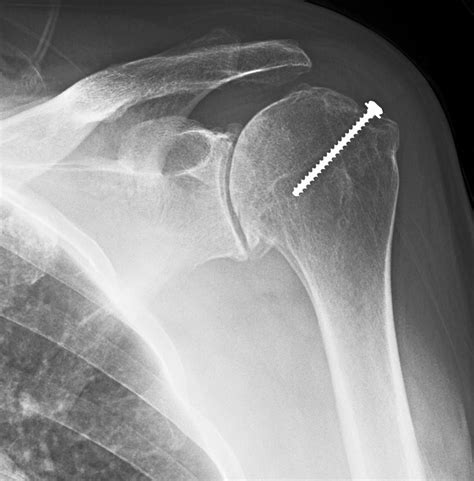

Shoulder Arthritis / Rotator Cuff Tears: causes of shoulder pain: X-rays for shoulder arthritis

Learn what to expect during a shoulder X-ray. This guide explains how this diagnostic imaging procedure identifies fractures, dislocations, or arthritis. Discover how medical professionals use these X-ray images to assess joint health, evaluate bone structures, and determine the best treatment plan for your shoulder pain or injury. Optimize your preparation for an accurate clinical diagnosis today.